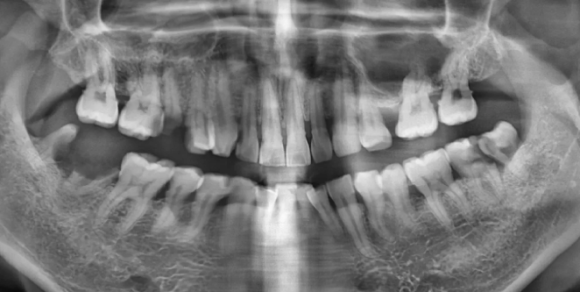

2024.02.13 초진 파노라마, (사진상 좌.우 반대)

- 충치 문제: 오른쪽 어금니(사진상 왼쪽)는 뿌리까지 충치가 심해 발치가 필요한 상태였습니다.

- 잇몸뼈 부족: 왼쪽 위 어금니(사진상 오른쪽)는 이 뽑은 후 잇몸뼈가 1~2mm밖에 남지 않을 것으로 예상되었는데요.

이 경우 임플란트 고정이 어렵기 때문에 뼈 이식과 상악동 거상술이 필요했습니다.

- 교합 불안정: 치아가 빠진 자리를 오랫동안 방치해 배열이 틀어지면서 치아 맞물림 상태가 매우 불안정해졌습니다.

치료 전 24.02.13

치료 후 24.10.05